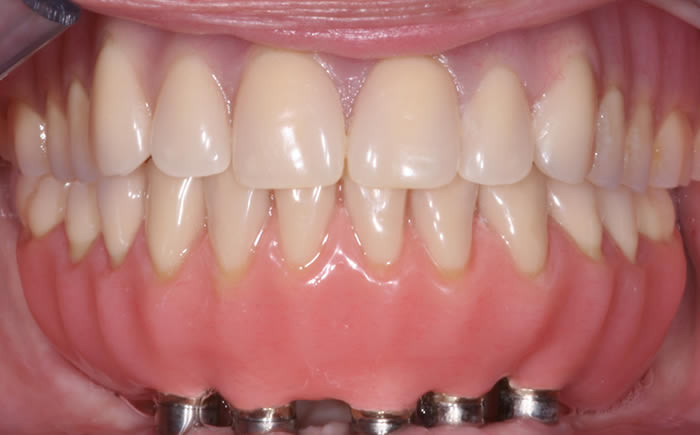

Full arches of teeth replaced by dental implants

Case One (5 images)

Full set of lower teeth fixed onto five dental implants.